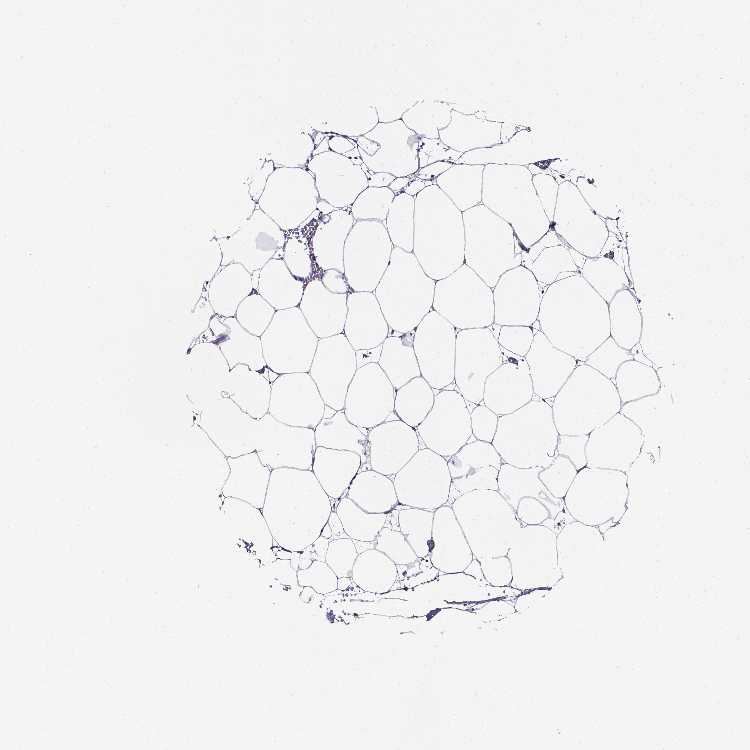

SOFT TISSUE 1 - Antibody stainingi

Antibody staining in the annotated cell types in the current human tissue is reported as not detected, low, medium, or high, based on conventional immunohistochemistry profiling in selected tissues. This score is based on the combination of the staining intensity and fraction of stained cells.

Each image is clickable and will lead to virtual microscopy that enables deeper exploration of all samples and also displays staining intensity scores, fraction scores and subcellular localization as well as patient and tissue information for each sample.

Antibody HPA020280Antibody CAB070163

Chondrocytes Not detectedNot detected

Fibroblasts Not detectedNot detected